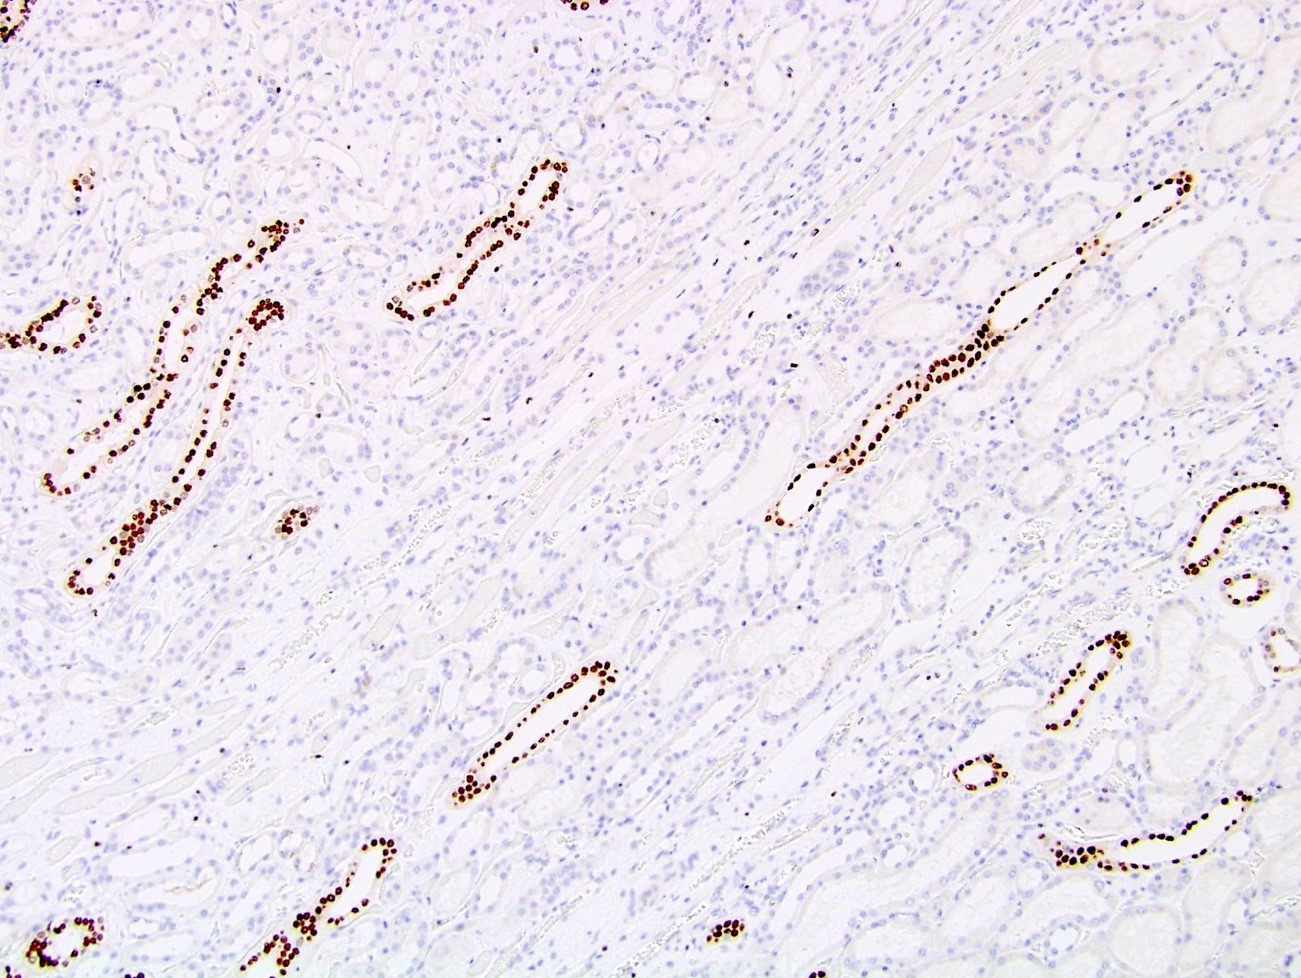

Positive staining - normal

- Distal convoluted tubules of kidney (Hum Pathol 2017;66:152)